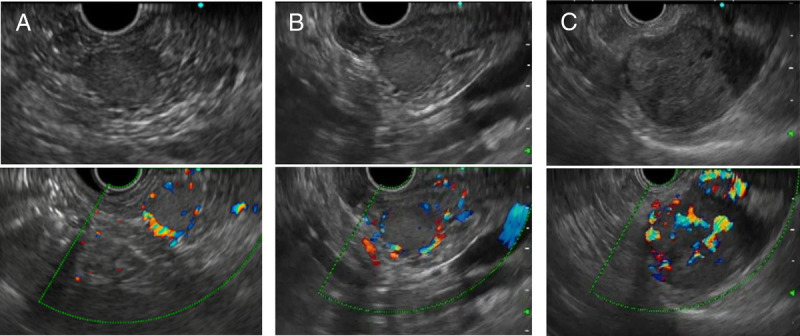

Contrast-enhanced harmonic EUS with time-intensity curve analysis useful for diagnosis of pancreatic metastasis from renal cell carcinoma (with videos).

对比增强谐波 EUS 与时间强度曲线分析有助于诊断肾细胞癌的胰腺转移(附视频)。